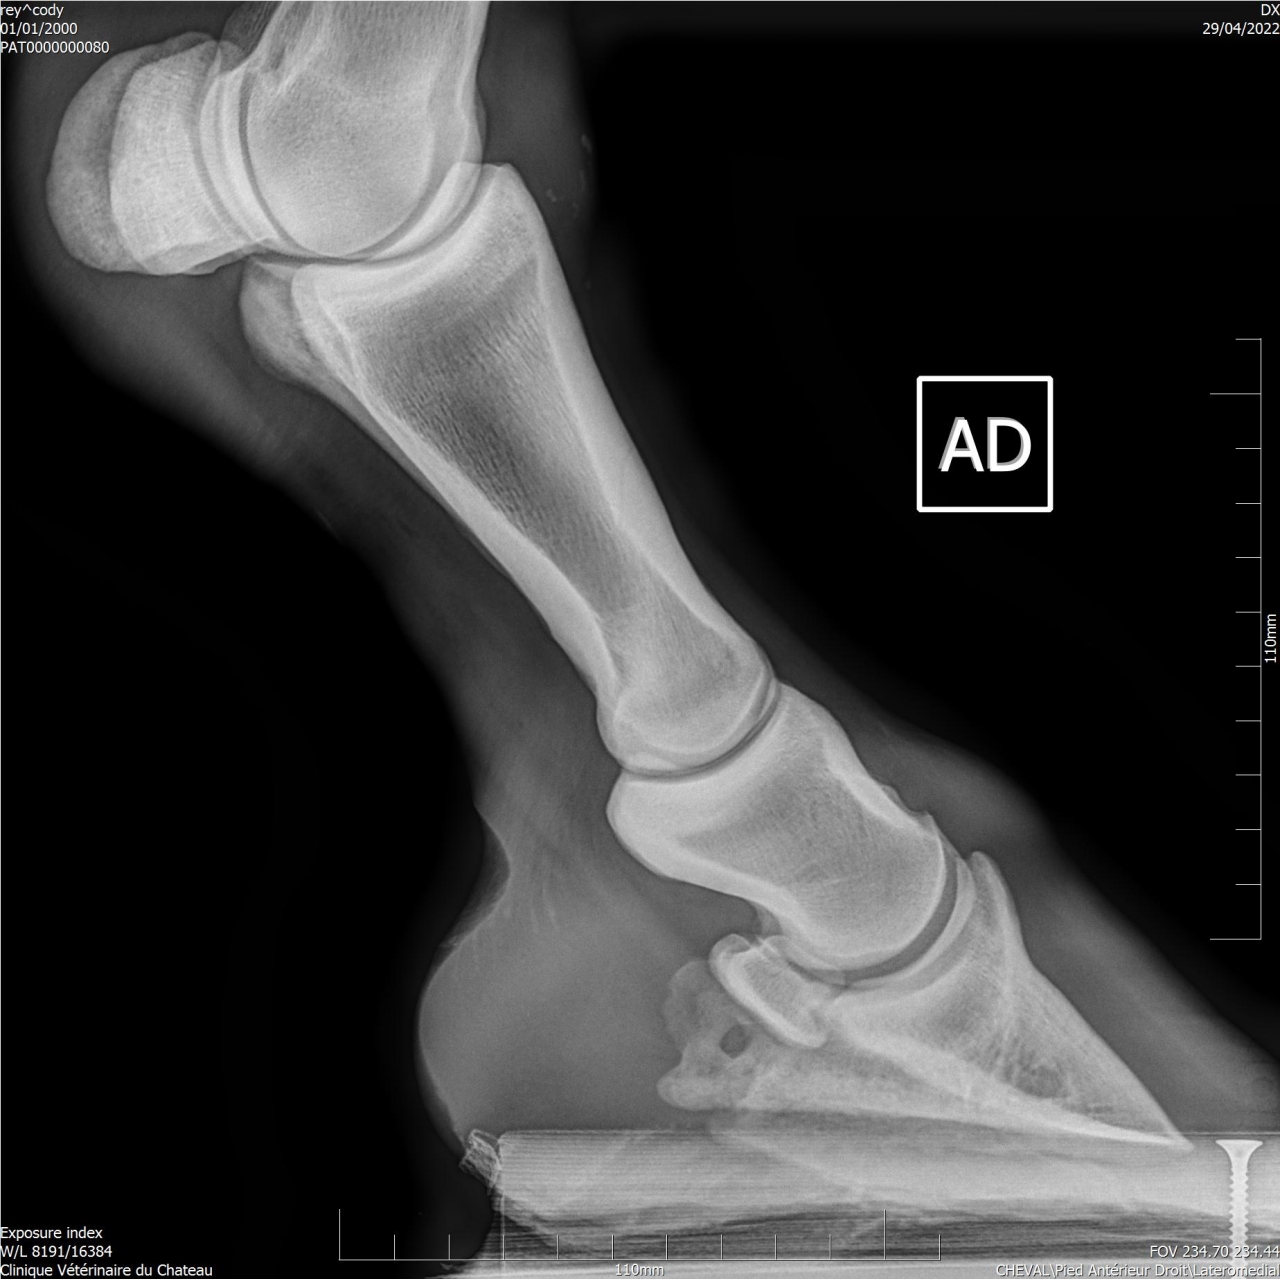

| Dire merci | Je remonte le post Mon cheval a été diagnostiqué naviculaire, il y a des fossettes synoviales. Ma véto préconise une infiltration avec du Tildren ou de l’Osphos. Aujourd'hui mon cheval a été ferré : antérieurs avec oignons et plaques en cuir, ferrure normale aux postérieurs. Voici les radios : ![]() ![]() ![]() ![]() ![]() |

| Dire merci | Les radios LM montrent une pince trop longue et pas de roll/ breakover Agir sur cela soulagera déjà énormément l’arrière du pied ! Sur la dp 60 on voit une zone noire circulaire Aurais tu une photos vue solaire stp ? Y a t’il fourmilière/évasement important voire un abcès récent ? |

| Dire merci | Je n'ai que ça comme radios ... Il y a des fourmilières aux 2 antérieurs. |